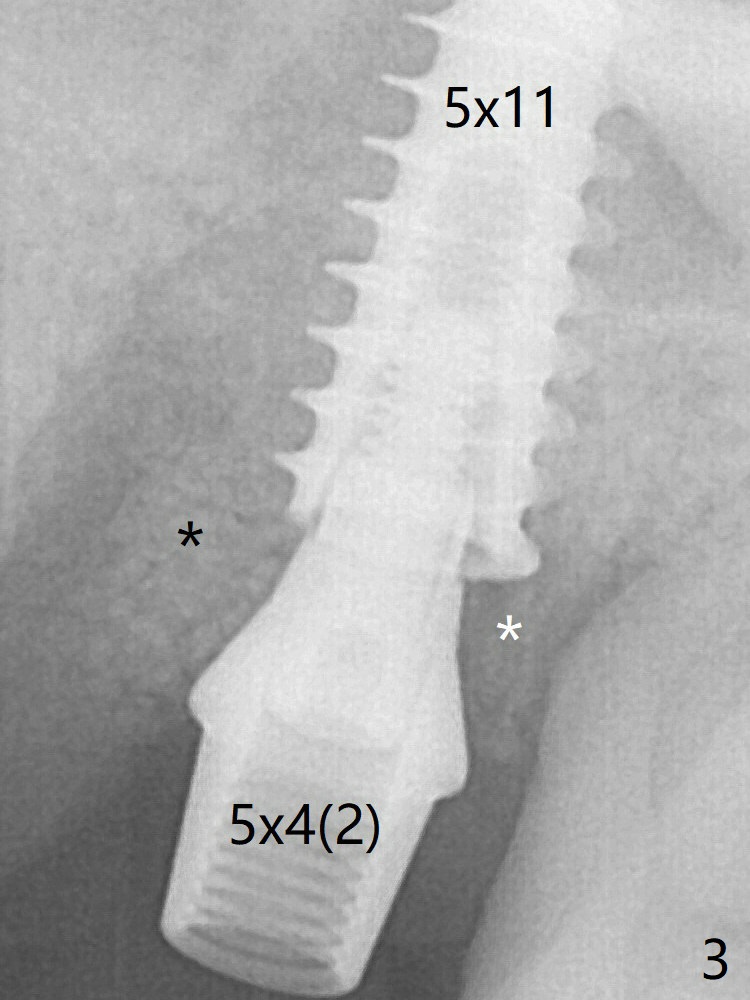

More of allograft (Fig.3 *) is placed prior to placement of 5x11 mm IBS implant (~30 Ncm). The latter is placed palatal. Last the allograft is placed palatal. A 5x4(2) mm abutment is placed to hold periodontal dressing in place. When the ridge is narrow, the implant should be small; 4 mm probably the most appropriate in this case. The implant seems to be osteotointegrated 3.5 months posotp (Fig.6).